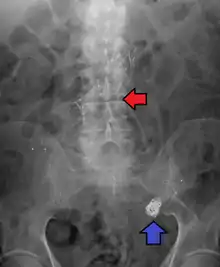

Abdominal aneurysm

Abdominal aortic aneurysm involves a regional dilation of the aorta and is diagnosed using ultrasonography, computed tomography, or magnetic resonance imaging. A segment of the aorta that is found to be greater than 50% larger than that of a healthy individual of the same sex and age is considered aneurysmal.[9] Abdominal aneurysms are usually asymptomatic but in rare cases can cause lower back pain or lower limb ischemia.